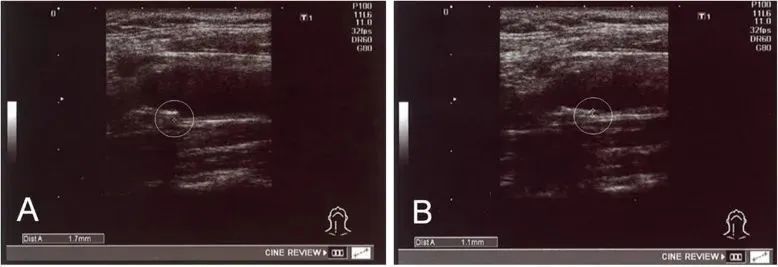

在《Stem Cell Res Ther》发表的一篇文章中,研究者收集了78名使用自体干细胞治疗动脉硬化的患者数据,包括他们给药前后的脂质分布、内膜中膜厚度 (IMT)等。

研究者对这些数据对比后发现:

①、12名在治疗前高密度脂蛋白值异常 (≤ 40 mg/dL) 患者,有 11 名 (91.7%) 在治疗后改善;

②、18例IMT值异常(≥1.1 mm)的患者,在治疗后IMT值均显著减少;

经过治疗,实验中一名患者 IMT 从 1.7 毫米降至 1.1 毫米